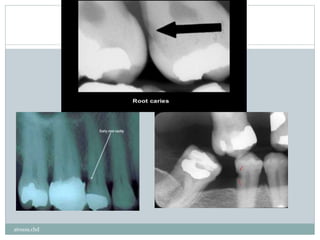

atousa.chd

‫تباطند‬‫ر‬‫ا‬‫در‬ ‫نیز‬ ‫لثه‬ ‫تحلیل‬ ‫با‬‫و‬ ‫کند‬ ‫می‬ ‫درگیر‬ ‫ا‬‫ر‬ ‫عاج‬‫هم‬‫و‬ ‫سمان‬ ‫هم‬ ‫ضایعات‬ ‫این‬.

‫تشخی‬ ‫ای‬‫ر‬‫ب‬ ‫ادیوگرفی‬‫ر‬ ‫اغلب‬ ‫شوند‬‫داده‬ ‫تشخیص‬ ‫بالینی‬ ‫نظر‬ ‫از‬ ‫باید‬ ‫ها‬ ‫پوسیدگی‬ ‫این‬‫ص‬

‫نیست‬ ‫نیاز‬.

‫اشتباه‬ ‫تفسیر‬:

‫است‬ Cervical burn out ‫با‬